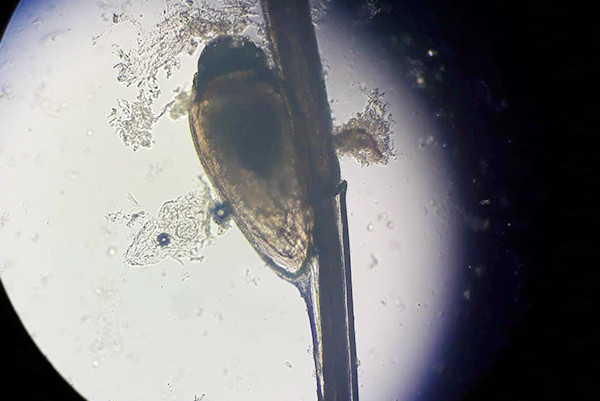

Người đàn ông bị rận ký sinh ở nách suốt 2 tháng

Người đàn ông 45 tuổi ở Nghệ An bị ngứa ngáy, khó chịu ở vùng nách. Kết quả nội soi cho thấy nhiều rận cùng ấu trùng bám trên da, lông.